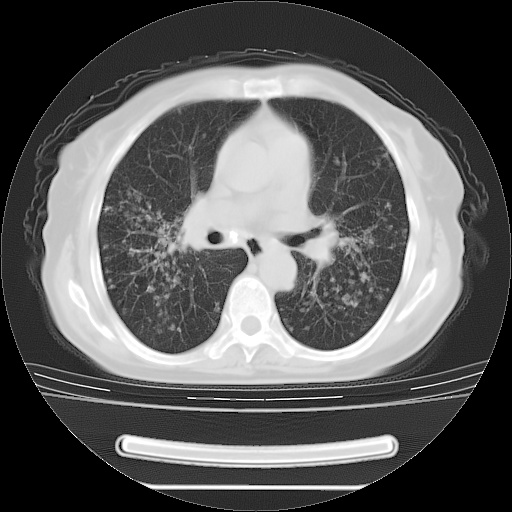

患者女性,72岁,慢性咳嗽3月余,曾抗炎治疗无效果,最近抗结核治疗约半月余,症状缓解。

ct示两肺粟粒状病灶,以两肺上叶尖后段及下叶背段分布为主;首先考虑结核。请战友们分析。

两肺内病灶呈小结节状和树芽状,纵膈的肿大的淋巴结密度不均匀,并见有钙化,考虑为两肺结核可能更大些。

两肺内病灶呈小结节状和树芽状,纵膈的肿大的淋巴结密度不均匀,并见有钙化,多形态病灶,考虑为两肺结核,肝内考虑小囊肿。

病灶以结节为主,大部分边界清楚,分布不均,病灶形态较单一,偶见空泡征,纵膈淋巴结肿大钙化,无结核中毒症状考虑 感染性病变【真菌类可能性大】,细支气管肺泡癌。其他待排

片子很好,质量很高,两侧肺门淋巴结肿大并有钙化,两肺弥漫病灶,首先考虑tb并播散,但年龄大了呀(72岁)小细胞肺癌不能除外,如果是肺癌也没什么大的治疗了,建议正规抗结核治疗后复查